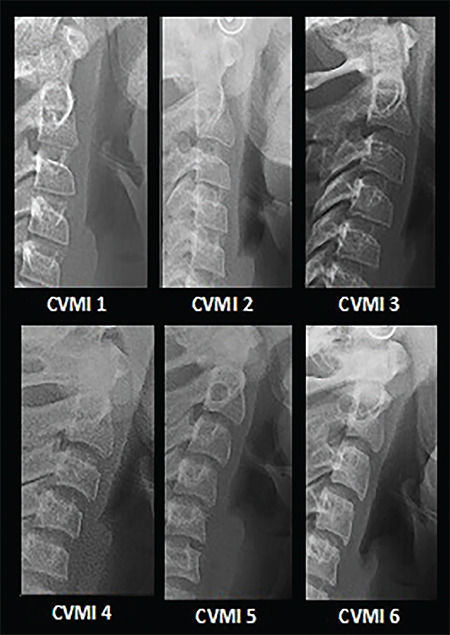

Methods: This retrospective study was conducted on panoramic and lateral cephalometric images of 406 female patients aged 9-14 years. The skeletal maturity and calcification stages of the mandibular canines, first premolars, second premolars, and second molars were determined using the Hassel-Farman and Demirjian (DI) methods, respectively. The prediction accuracy of the peak pubertal stage with the studied teeth was assessed using a receiver operating characteristic curve and the area under the curve (AUC). The DI stage of H was designated as the reference level, and Bayesian logistic regression analysis was used to assess the coinciding chance of each DI stage and peak pubertal stage.